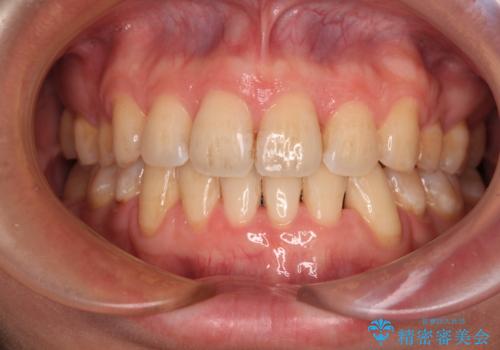

[ マウスピース矯正 ] 出っ歯に見える前歯を改善したい

![[ マウスピース矯正 ] 出っ歯に見える前歯を改善したいの症例 治療前](https://seimitsushinbi.jp/wp/wp-content/uploads/2023/10/IMG_6858-500x350.jpg?v=1697014973)

![[ マウスピース矯正 ] 出っ歯に見える前歯を改善したいの症例 治療後](https://seimitsushinbi.jp/wp/wp-content/uploads/2023/10/8a6c9bf89570c0c75da0a5fabd1cd70e-500x350.jpg?v=1697014858)